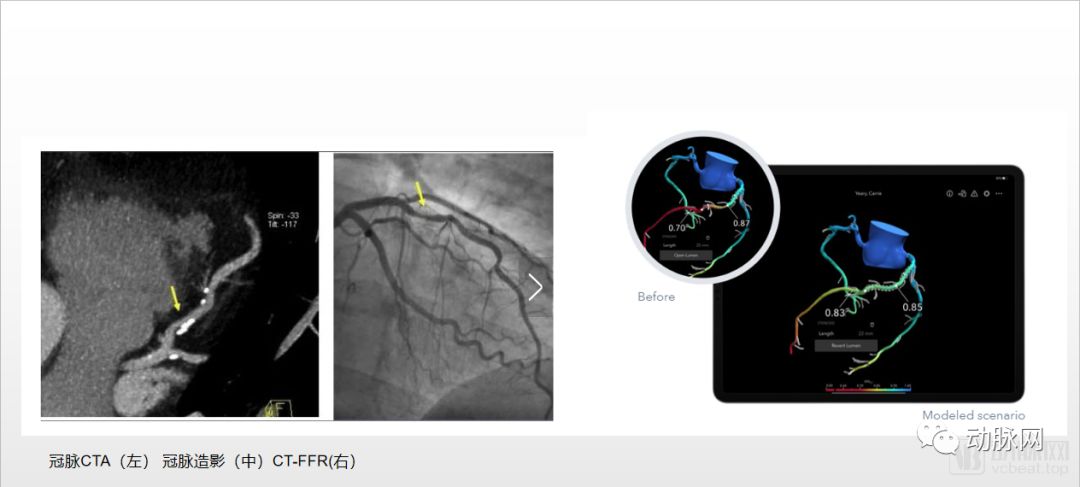

在实现心脏“4D”可视的过程,适用于慢性冠心病的基于医学影像测算冠状动脉血流储备分数(FFR)是目前较成熟的技术,其中主要的技术是CT-FFR和QFR。

基于医学影像测算FFR这一诊断方式的横空出世,则是弯道超车为医生提供了另一种测量方法。无创FFR诊断无需昂贵的压力导丝伸入血管,CT-FFR、QFR等方式可以基于影像测算FFR, 直接从CT、冠脉造影、OCT、IVUS等影像数据上重建冠状动脉的三维形状,再计算出血流动力。

CT-FFR是根据CT影像进行器官 三维重建 ;而QFR是通过冠脉造影图像进行 三维重建 计算FFR;OFR则是根据OCT影像进行计算。

对于CT-FFR来说,行业标杆性企业HeartFlow的产品应用场景是充当导管室的“守门人”,帮助医生判断患者是否需要进行冠脉造影筛查,减少不必要的侵入式冠脉造影检查,帮助医生制定最佳的治疗方案,由此减少医疗卫生费用支出。

从具体的技术细节来看,CT-FFR目前是利用CT影像,同时利用流体动力学的原理,计算出血液的速度和压力,从而计算出三维的FFR。

CT-FFR技术的处理流程包括CT建模、冠脉三维重构、血液动力学分析等。其中会涉及AI智能图像识别、图形 图像处理 、血动力仿真相关技术。